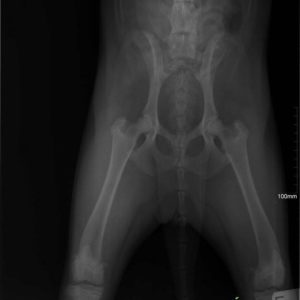

Ismét hálával van teli a szívünk- köszönjük Alexander Englertnek, hogy Zora műtétjét finanszírozta!

Zora túl van a műtéten és 5 nap után újra velünk van a menhelyen! A kedve jó, nincsenek fájdalmai és reméljük a 2 hónap pihenő után végre felszabadultan játszhat majd a többiekkel!